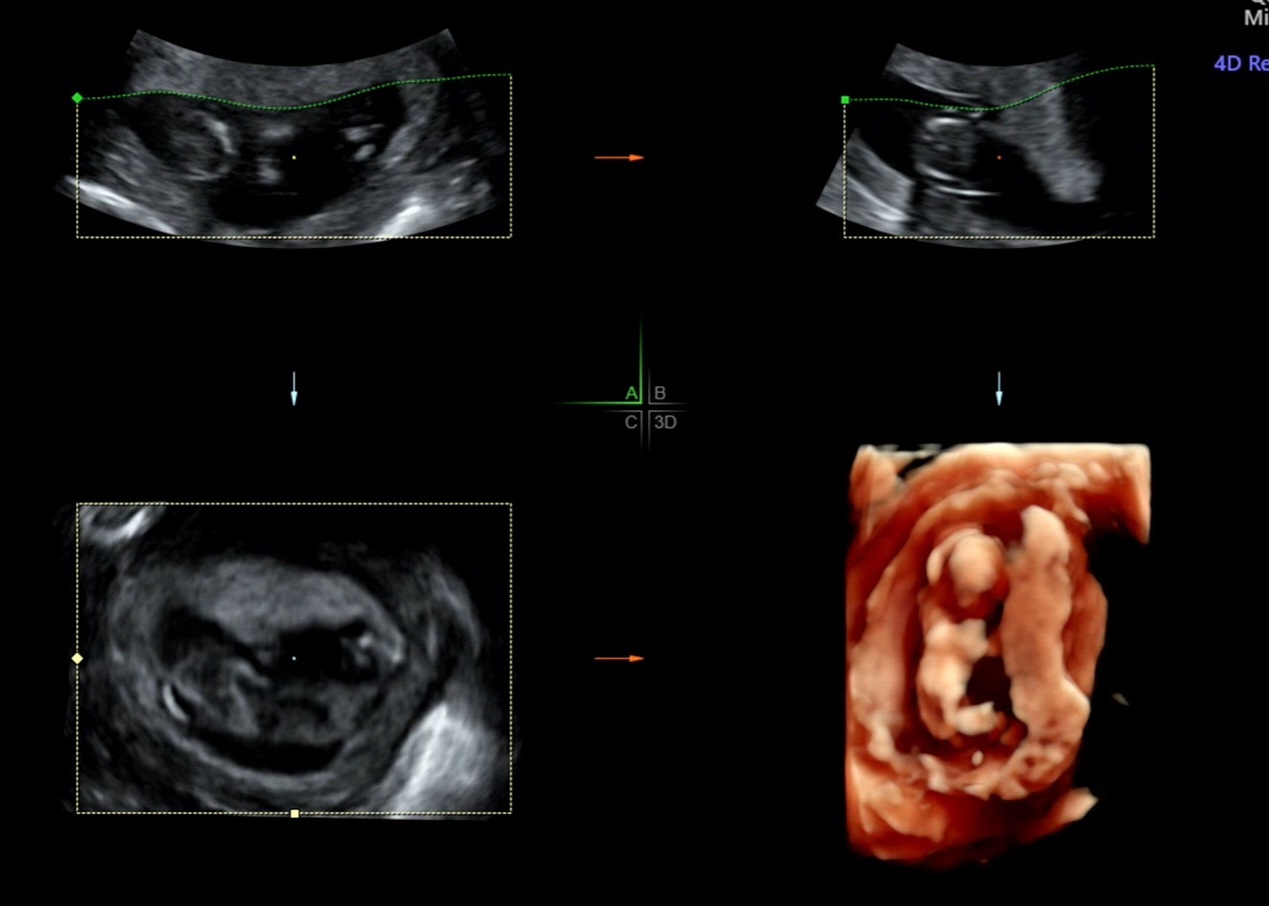

👆 이제는 제법 사람의 모습이 많이 보였던 12주 4일차👆

임신 12주에 했던 초기 정밀 초음파

도담이가 얼굴을 보여주지 않을까 봐 초코라떼도 먹고 밥도 잘 챙겨 먹었는데

얼굴 보기가 쉽지 않았어요 ㅠㅠ 그래서 초음파 선생님께서 한 10분 넘게

배를 흔들고 저도 자세를 계속 바꾸면서 드디어 도담이 얼굴을 볼 수 있었어요

목 투명대와 코뼈 모두 정상이라 초기 정밀 초음파는 통과했습니다!!